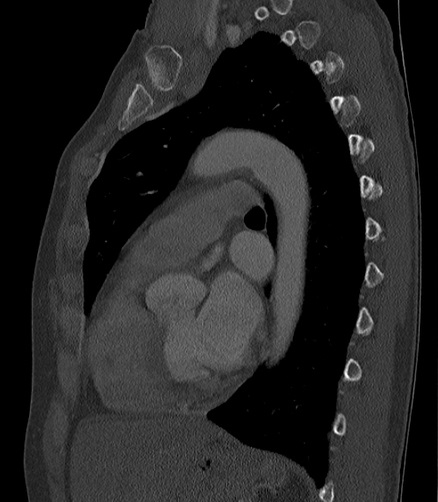

Même cas en coupe TDM fenêtre

mediastinale |

Et en coupe TDM sagital fenetre

mediastinal osseuse |